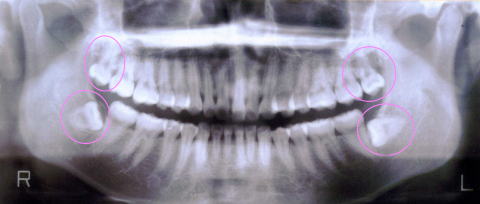

親知らずは20歳前後に生えてきます。現在60歳の私は上の親知らずは虫歯になったので25歳の頃に抜歯してもらいました。下の親知らずは2本とも横に向いて半分生えている状態ですが、抜くのが怖いので、頑張って虫歯にならないように1日5回以上全体の歯を磨いています。私は口腔外科出身なので口腔外科の7年間とその後5年間ぐらいの期間に1,000本以上は抜いてきましたが、現在は済生会千里病院(南千里)に紹介状を書いて抜いてきてもらう事にしています。年間30人ほどは紹介させて頂いています。ご希望があれば紹介状をお書きします。

下は神経に触ると「唇のしびれ」や「唇の周辺の知覚麻痺」が起こるので、やはり現役の口腔外科の先生の方が安心だと私は思います。私も口腔外科で多くの患者さんを診させてもらい、安全の教育を最優先に受けたこともあり、患者さんの安全を優先し当院では無理はしないことにしています。